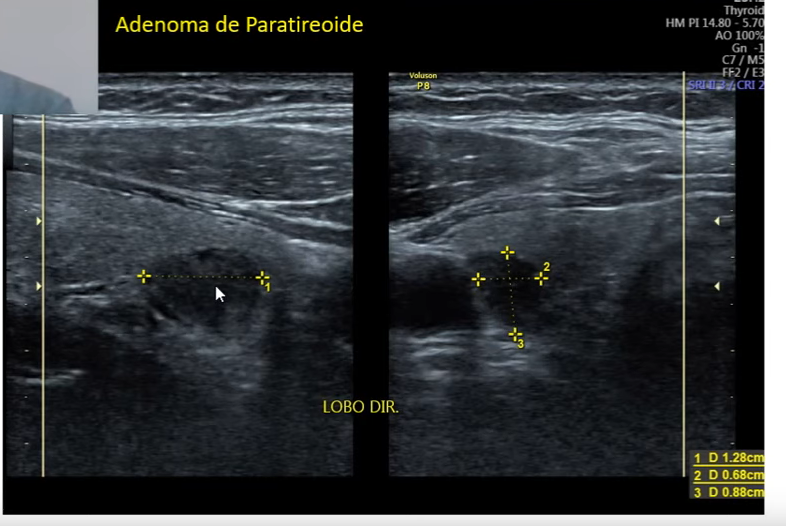

Qual o nódulo mais comum de paratireoide ?

Normalmente são adenomas